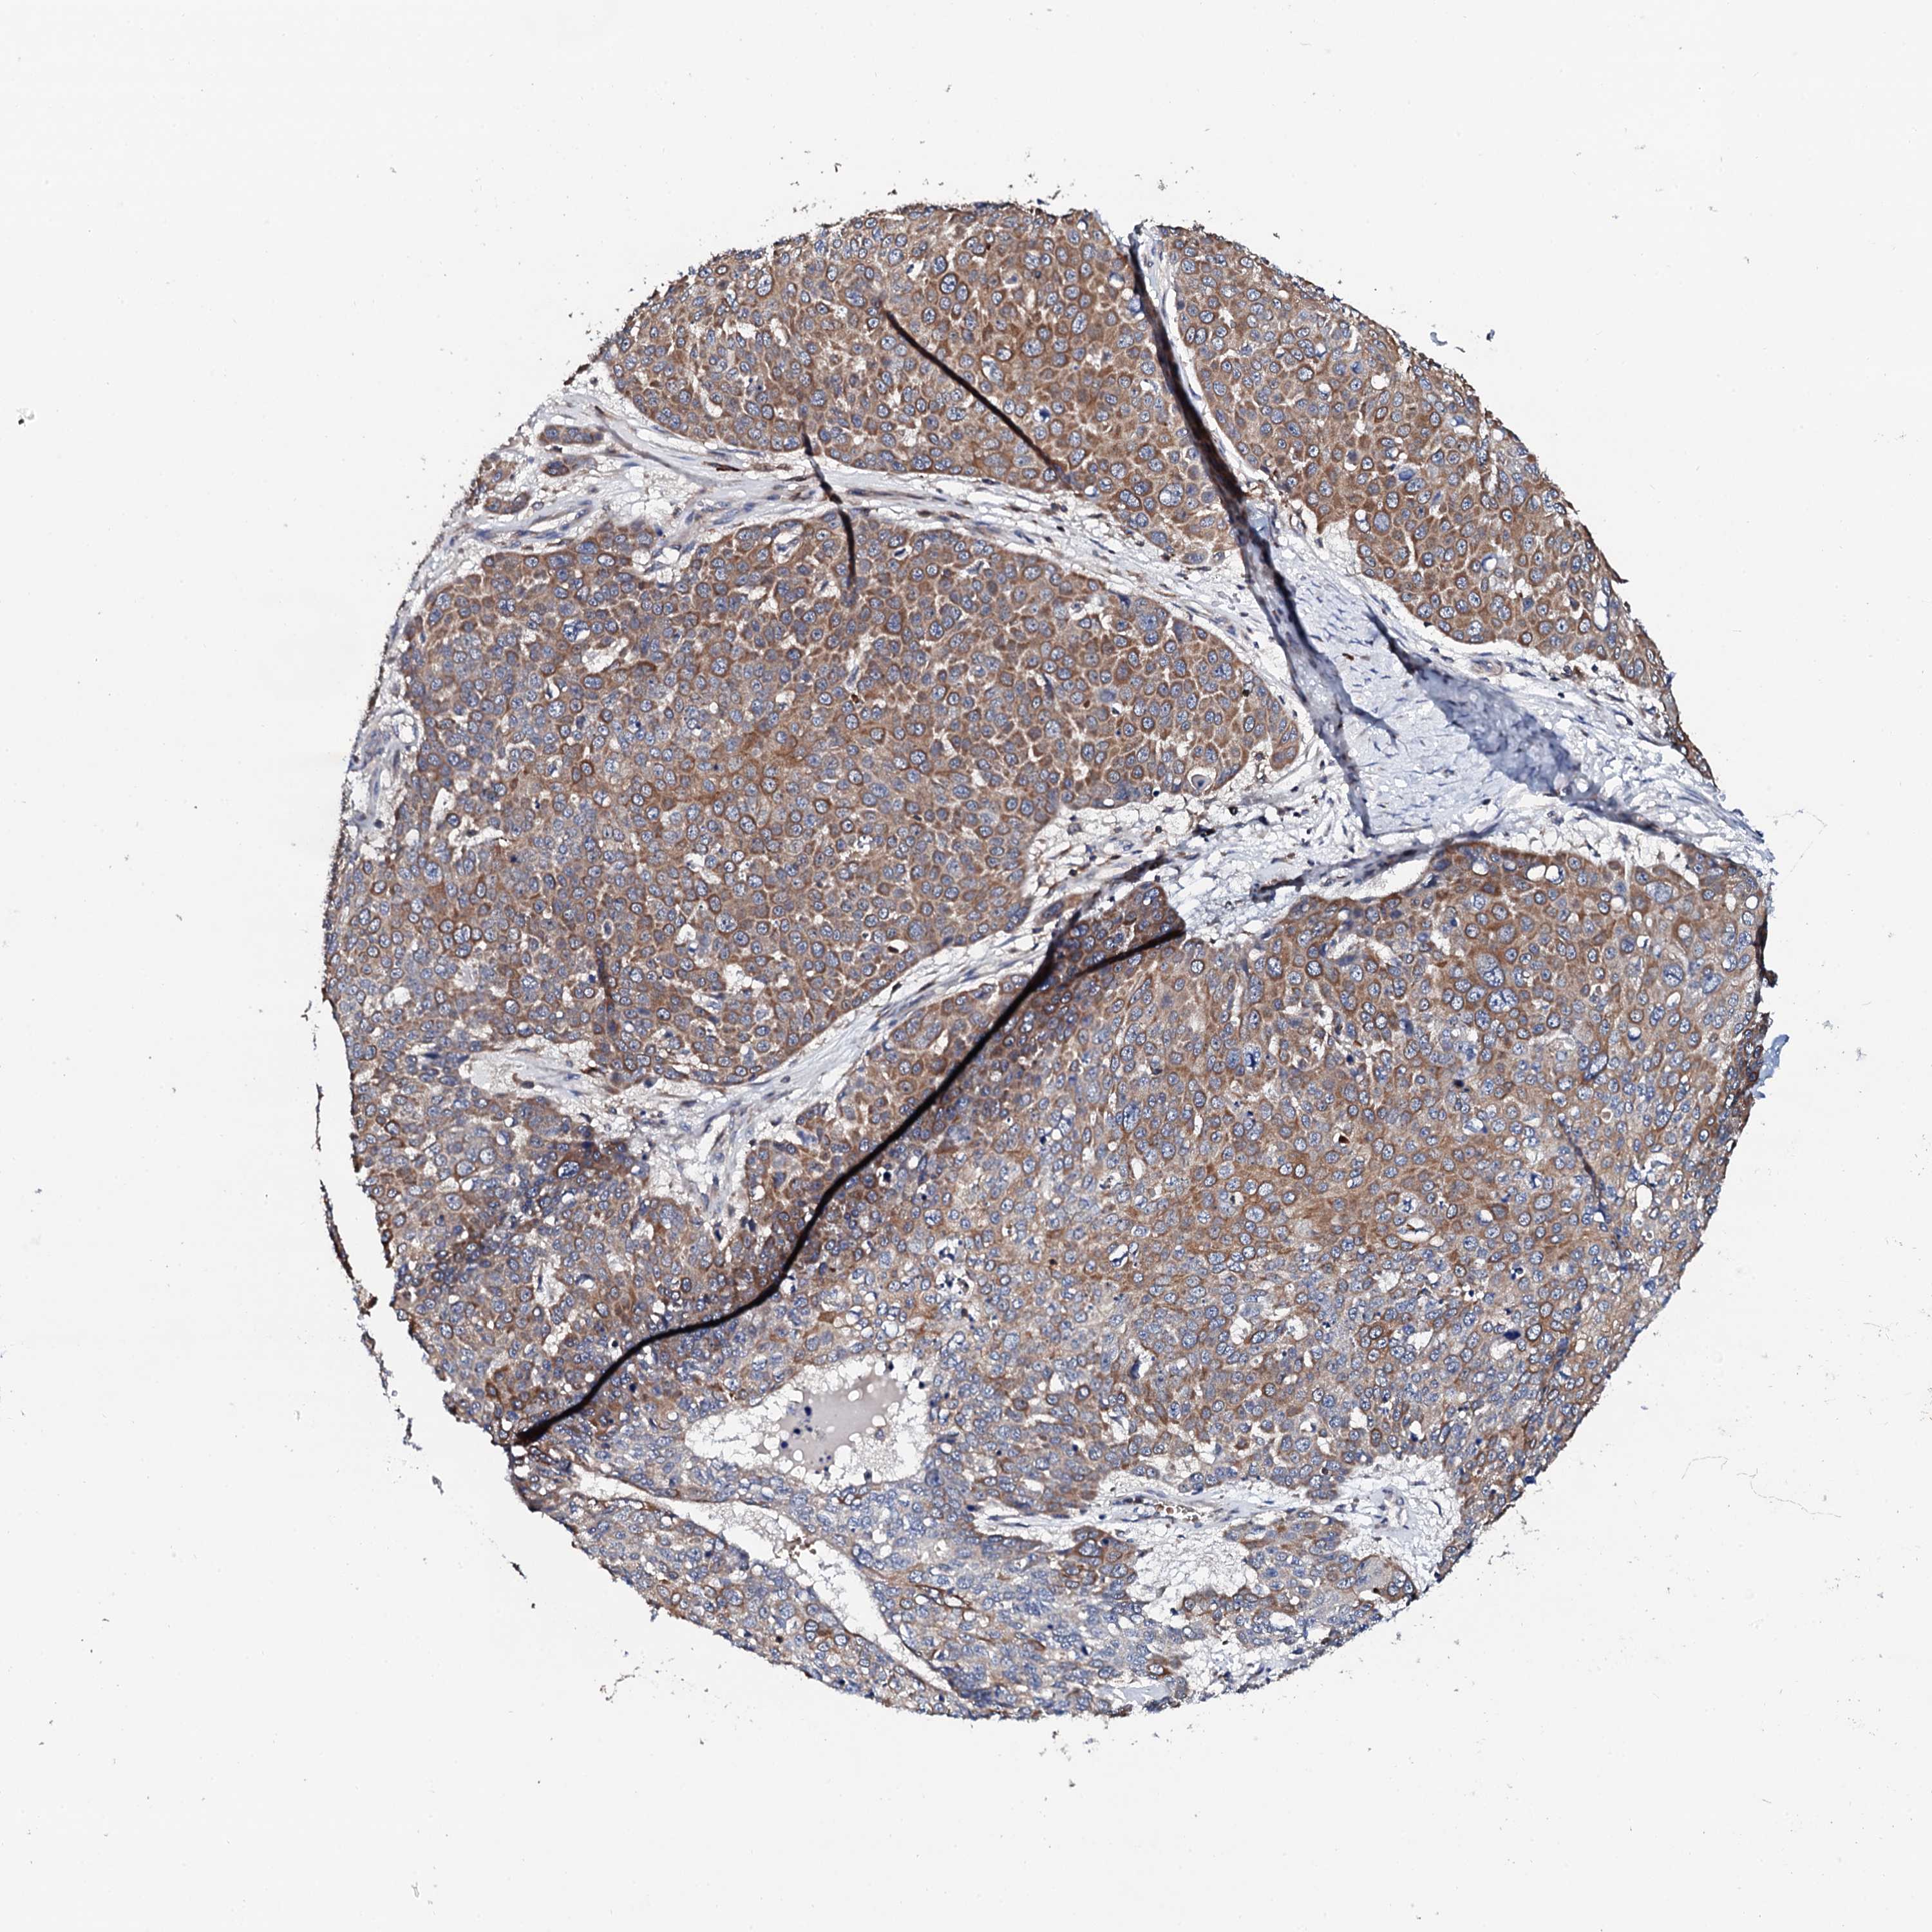

SKIN CANCER - Protein expressioni

A mouse-over function shows sample information and annotation data. Click on an image to view it in a full screen mode. Samples can be filtered based on level of antibody staining by selecting one or several of the following categories: high, medium, low and not detected. The assay and annotation is described here.

Antibody stainingi

Antibody staining in the annotated cell types in the current human tissue is reported as not detected, low, medium, or high, based on conventional immunohistochemistry profiling in selected tissues. This score is based on the combination of the staining intensity and fraction of stained cells.

Each image is clickable and will lead to virtual microscopy that enables deeper exploration of all samples and also displays staining intensity scores, fraction scores and subcellular localization as well as patient and tissue information for each sample.

Antibody HPA040924

Antibody HPA042539

Staining

High

Medium

Low

Not detected

Intensity

Strong

Moderate

Weak

Negative

Quantity

>75%

75%-25%

<25%

None

Location

Nuclear

Cytoplasmic/membranous

Cytoplasmic/membranous,nuclear

Basal cell carcinoma

Squamous cell carcinoma, NOS

Squamous cell carcinoma, metastatic, NOS